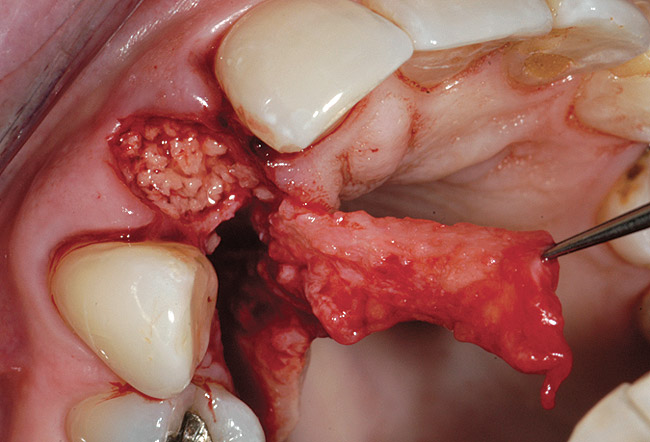

A 26-year-old woman was referred for evaluation and treatment of a fractured maxillary left central incisor. Clinical and radiographic examination revealed a fractured endodontically treated tooth with a fistulous tract in the labial vestibule (Figure 26). Also noted were a flat, thick periodontal biotype, a medium smile line, and a complete loss of labial plate. Atraumatic tooth removal using a periotome and thin-beaked forceps revealed the extent of soft- and hard-tissue loss (Figure 27). Initial treatment consisted of a mineralized bone allograft (MinerOss), along with soft-tissue grafting (connective tissue graft and free gingival graft) (Figure 28 and Figure 29). Reevaluation 9 months later revealed regeneration of a thicker labial plate that was still deficient in both width and height for conventional root-form implant placement. A mandibular block graft harvested from the symphysis was used as Phase II treatment (Figure 30). After 4 months, a root-form implant was placed in a nonsubmerged mode (Figure 31) in preparation for provisional crown fabrication (Figure 32).

Figure 27  Post-extraction socket defect. Note the extent of soft-tissue dehiscence and complete loss of labial plate.

Figure 27

Figure 28  Connective tissue graft in place.

Figure 28

Figure 29  Socket graft completed with mineralized bone allograft, connective tissue graft, and two free gingival tissue grafts.

Figure 29

Figure 30  Mandibular block graft for lateral bone augmentation, 4 months after initial socket grafts.

Figure 30